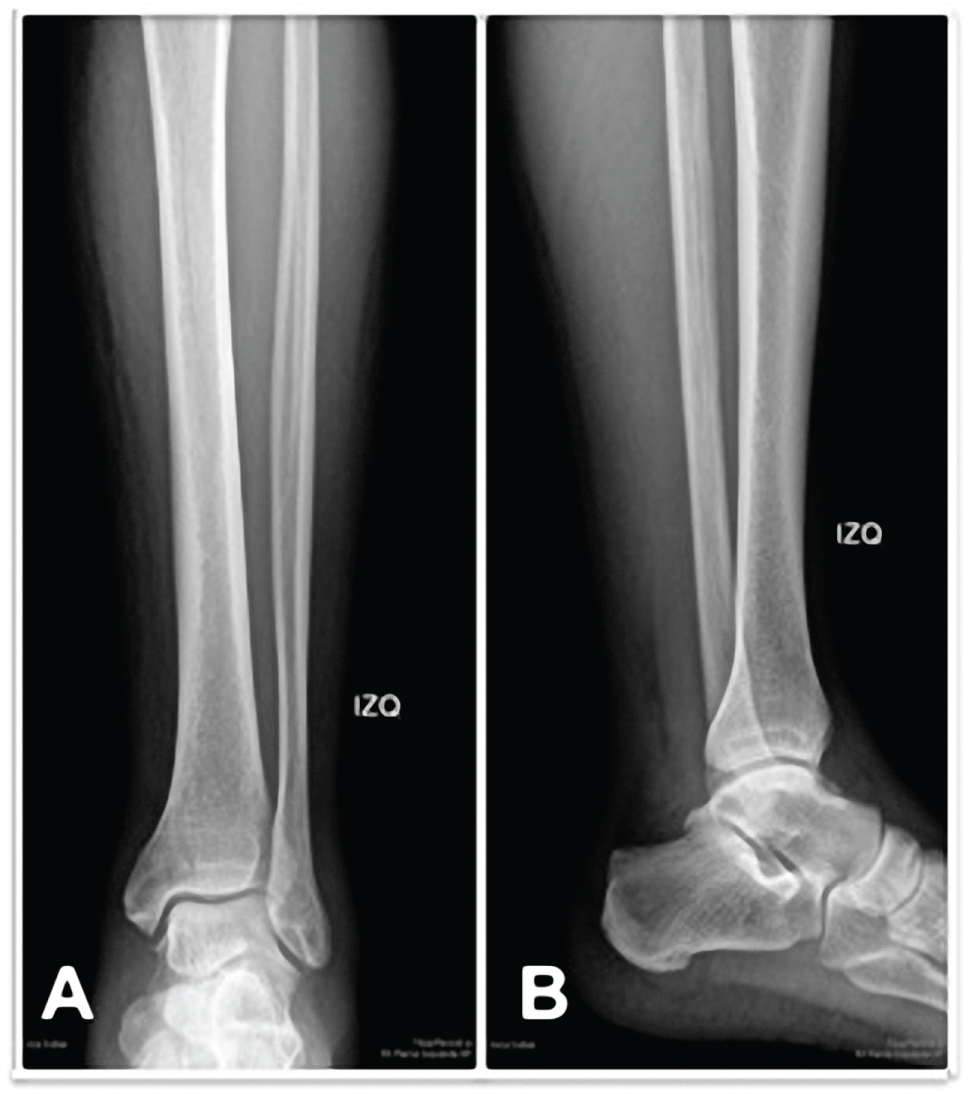

The patient's x-rays were reviewed, and a questionable radiolucent line was seen in the medial malleolus consistent with a fracture that had not been initially diagnosed (Figure 1). Ankle Computed tomography (CT) was performed, confirming the diagnosis (Figure 2).

Figure 1: Ankle radiograph at presentation (A) anteroposterior view; (B) lateral view, Radiolucent line is seen in the medial malleolus. View Figure 1